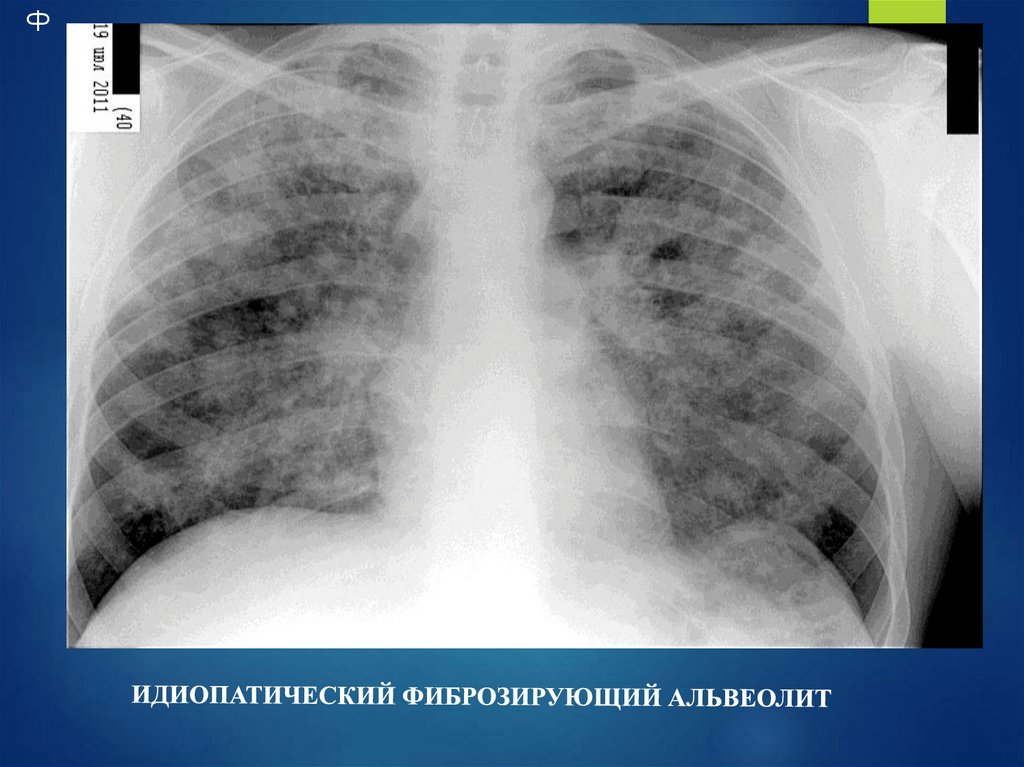

Ф

Сотовое легкое (часто осложняется

пневмотораксом)